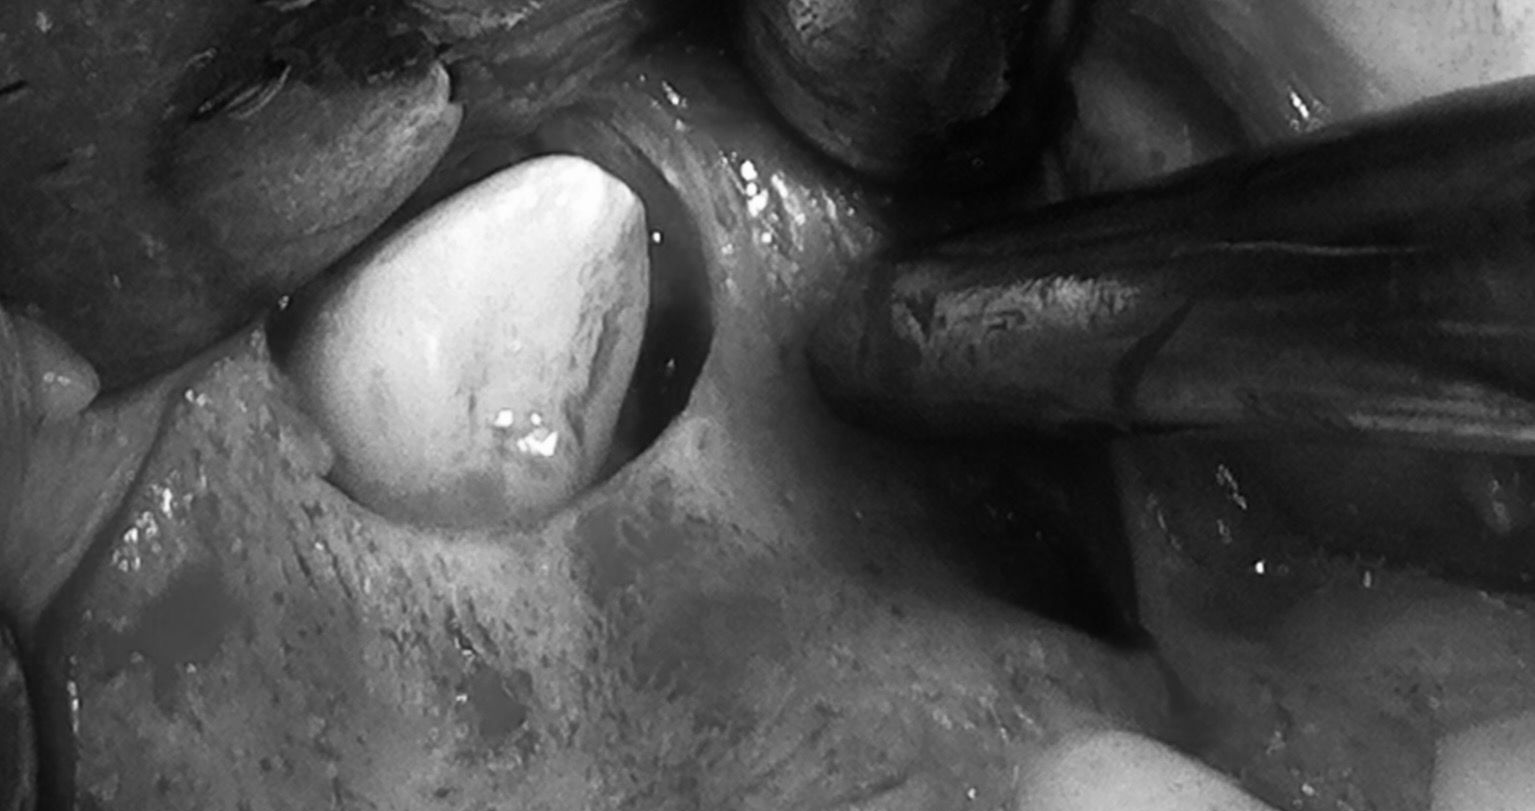

Rimozione chirurgica del canino incluso

Visione post estrattiva